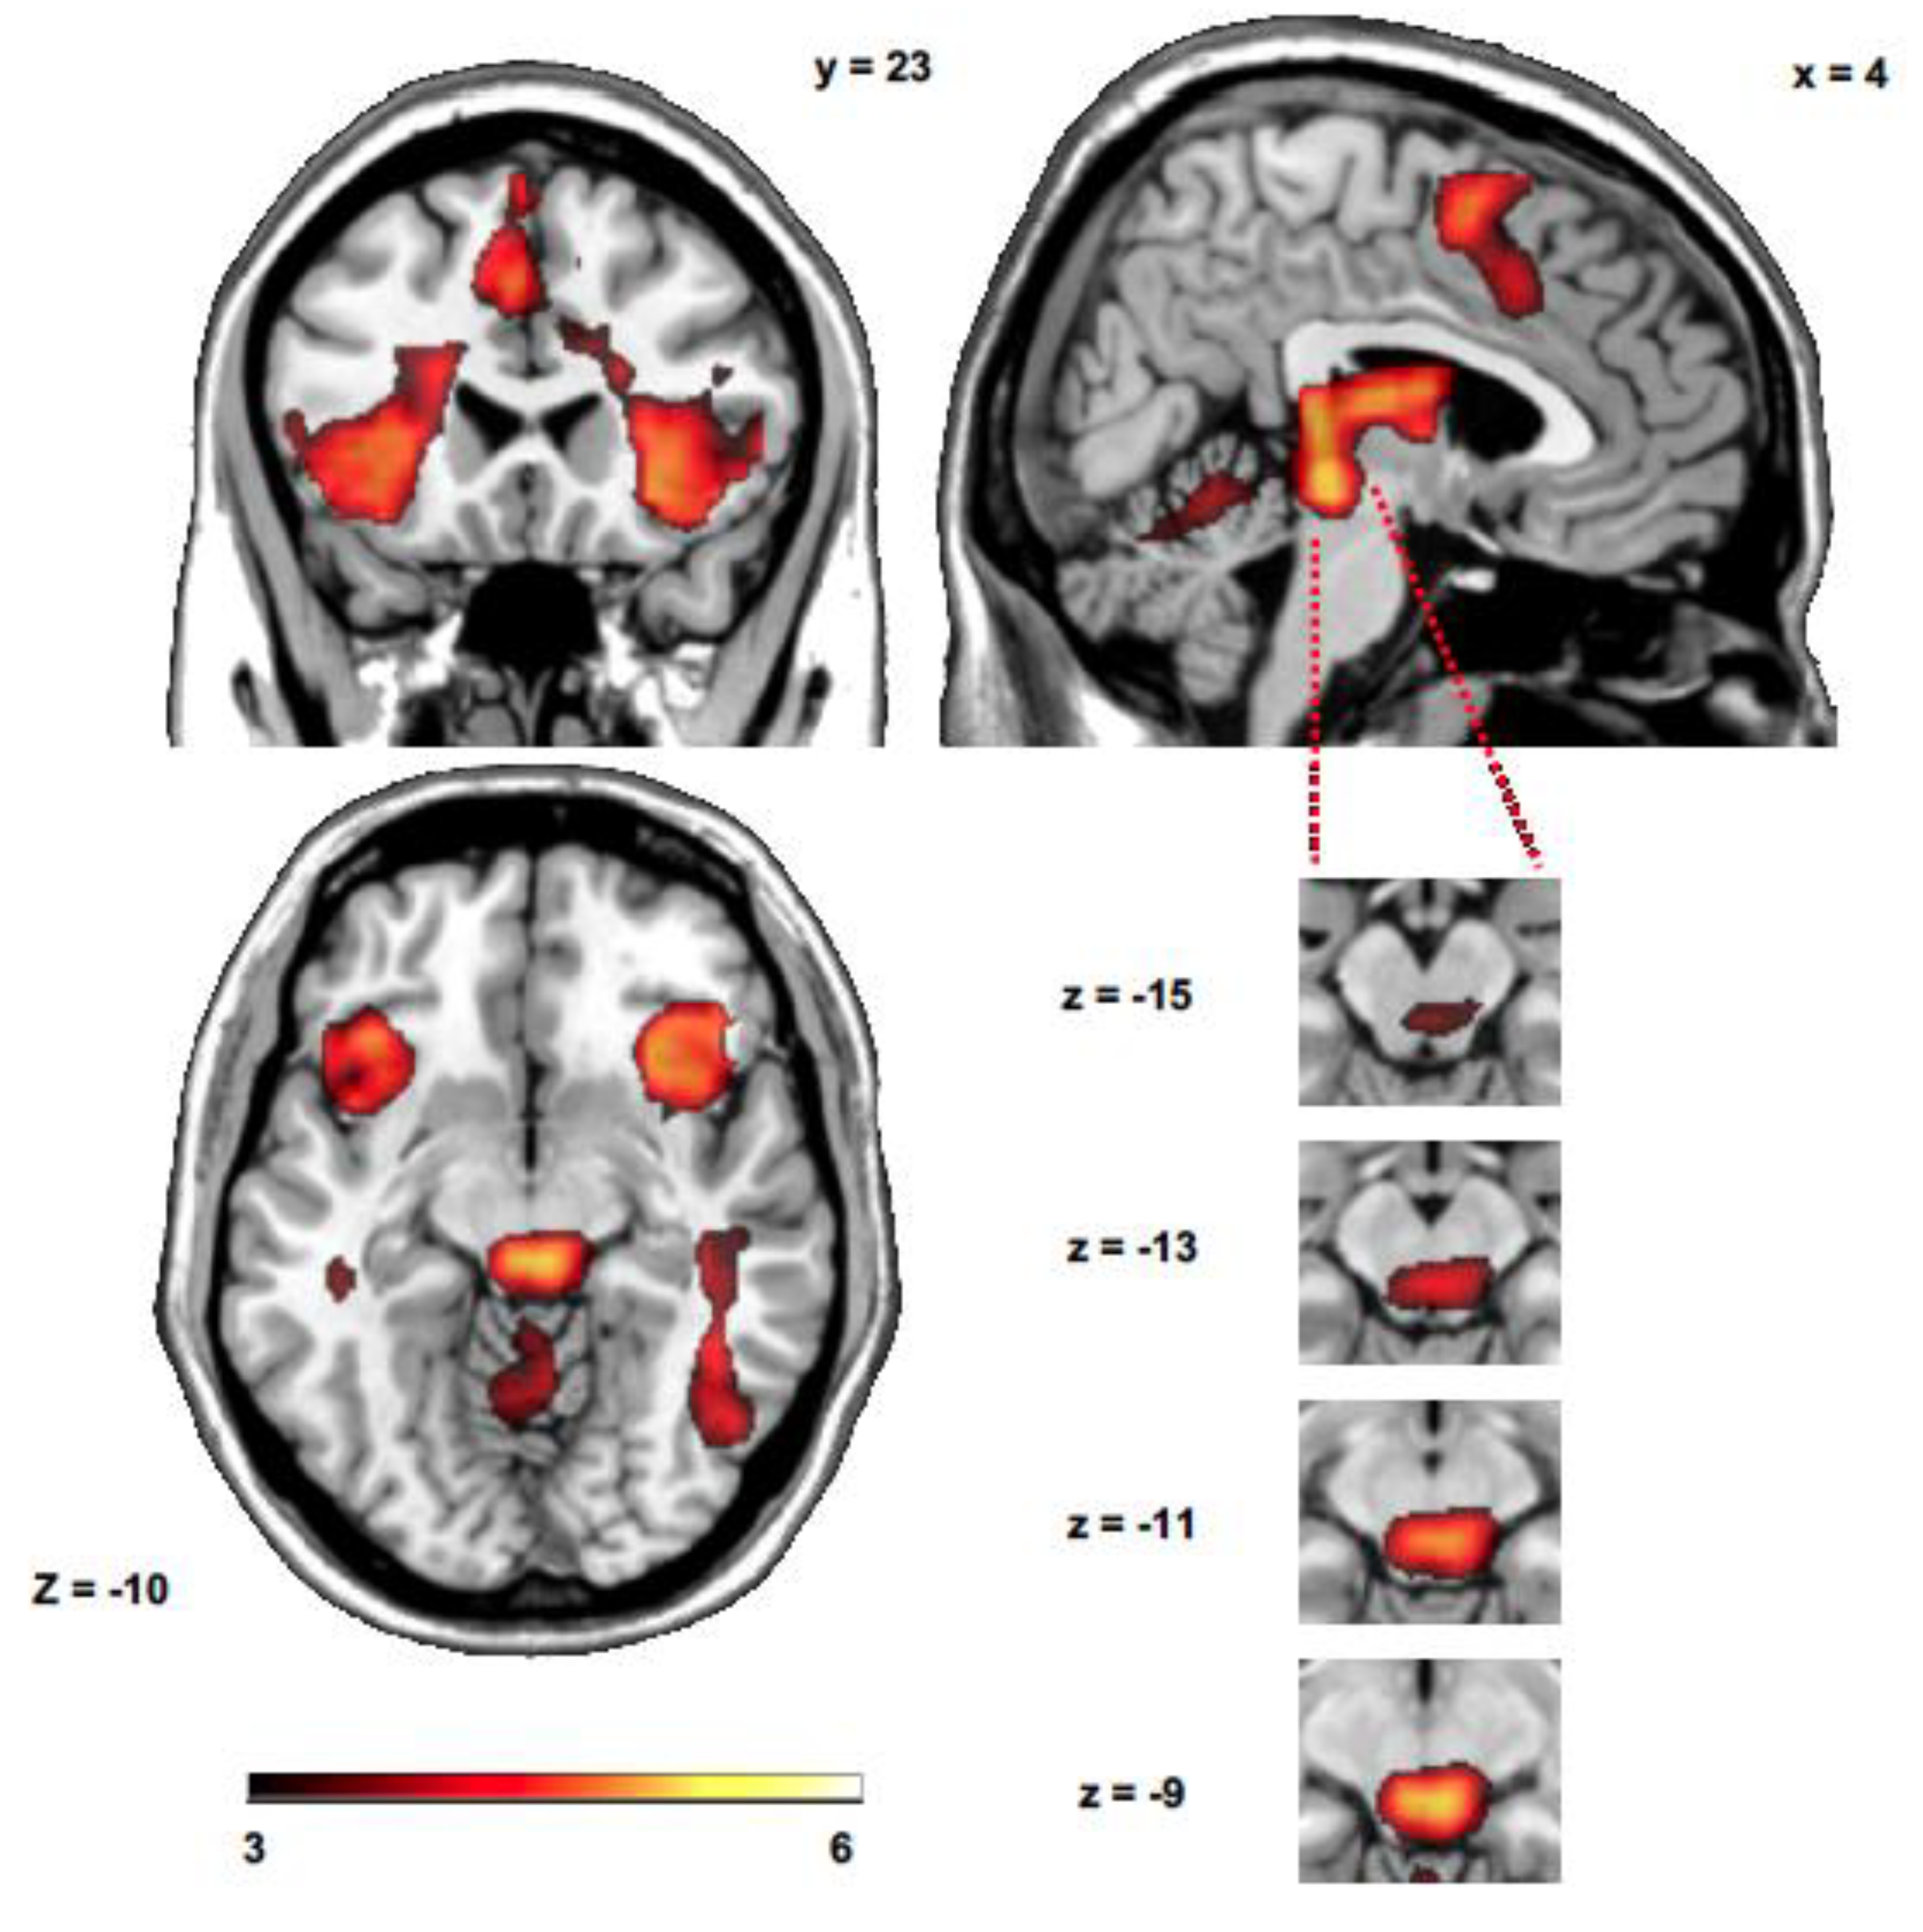

3.2. Whole Brain Group Analysis

| Up > Down | ||||

|---|---|---|---|---|

| K | T | x, y, z (mm) | Hemisphere | Area |

| 200 | 5.88 | −8, 10, 65 | L | SMA |

| 92 | 5.62 | 45, −66, 0 | R | Middle temporal gyrus |

| 81 | 5.28 | −37, 0, 50 | L | Premotor cortex |

| 62 | 5.14 | 5, −26, −10 | R | Midbrain |

| 39 | 5.03 | 18, −10, 25 | R | Caudate nucleus |

| 77 | 4.98 | 42, 0, 50 | R | Premotor cortex |

| 114 | 4.87 | −37, 20, 0 | L | Anterior insula |

| 107 | 4.70 | 42, 13, 5 | R | Anterior insula |

| 47 | 4.19 | 2, −19, 5 | R | Thalamus |